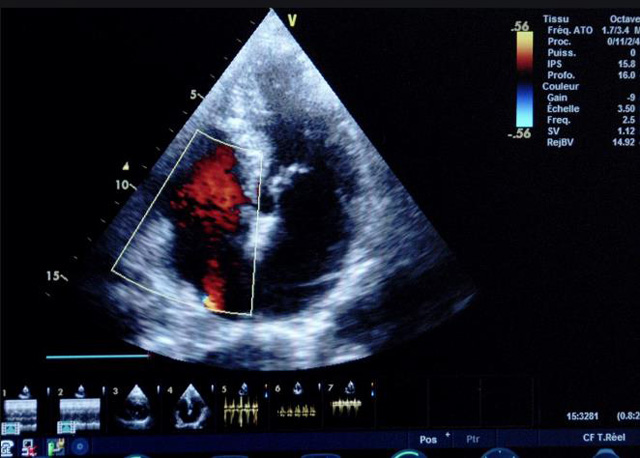

二、彩色室壁運(yùn)動分析

(一)基本原理彩色室璧運(yùn)動分析,從整體散射數(shù)據(jù)中識別心內(nèi)膜邊界,并與前一幀彩色不同,心臟收縮或舒張期開始到結(jié)束時(shí)心內(nèi)膜的全部過程。每一次順序顯示結(jié)束后,原來的彩色自動消失,以便進(jìn)入下一個(gè)顯示過程。其結(jié)果是獲得對應(yīng)于每一個(gè)心動周期的彩色顯示,描繪特定周期內(nèi)室壁運(yùn)動的時(shí)間運(yùn)動軌跡。

(二)操作步驟根據(jù)背向散射數(shù)據(jù)中將心內(nèi)膜運(yùn)動的位移過程分類為組織或血液的原理,邊緣檢測跟蹤心內(nèi)膜和血液的界面。橙色表示收縮期的開始,收縮期不同時(shí)相逐幀顯示色彩均疊加在收縮末期最后一幀圖像中。檢查時(shí),可按以下步驟進(jìn)行:

①顯示較為理想的二維圖像,常用切面有心尖四腔心、二腔心、左心室長軸和左心室乳頭肌水平短軸切面。

②啟動AQ系統(tǒng),啟動后適當(dāng)?shù)卣{(diào)節(jié)增益補(bǔ)償,顯示心內(nèi)膜。

③啟動CK系統(tǒng),啟動后劃定感興趣區(qū)域。同時(shí)記錄的心動圖R波頂點(diǎn)為舒張末期,T波終點(diǎn)為收縮末期,顯示RT間期的CK彩階圖,連續(xù)記錄3~ 5個(gè)心動周期。